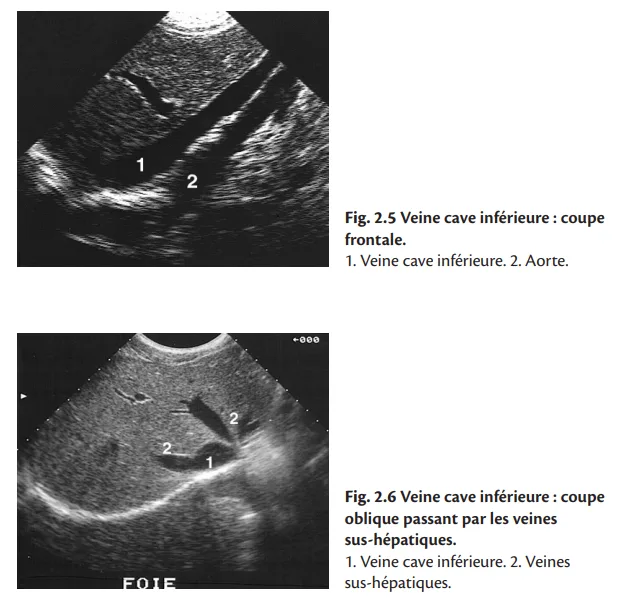

Elle naît au niveau de L5, de la réunion des deux veines iliaques primitives, et monte ensuite le long du flanc droit du rachis, jusqu'à son abouchement dans l'oreillette droite. Elle reçoit principalement, au cours de son trajet abdominal, les veines rénales et les veines sus-hépatiques (fig. 2.5 à 2.8).

Le sujet étant en décubitus dorsal puis en oblique postérieure gauche, on pratique des coupes sagittales, passant par le grand axe de la veine cave inférieure, et des coupes transversales. Les collatérales sont étudiées pour les veines rénales en coupe transversale et pour les veines sus-hépatiques en coupe oblique sous-costale.

En coupe transversale, la section de la veine cave inférieure est ovalaire, ses bords sont fins et nets, son calibre varie au cours du cycle respiratoire : il est maximum en inspiration bloquée (manœuvre de Valsalva) et minimum, voire collabé, en fin d'expiration. Cette cinétique est un critère important de normalité hémodynamique. Le diamètre en expiration profonde ne doit pas dépasser 25 mm.